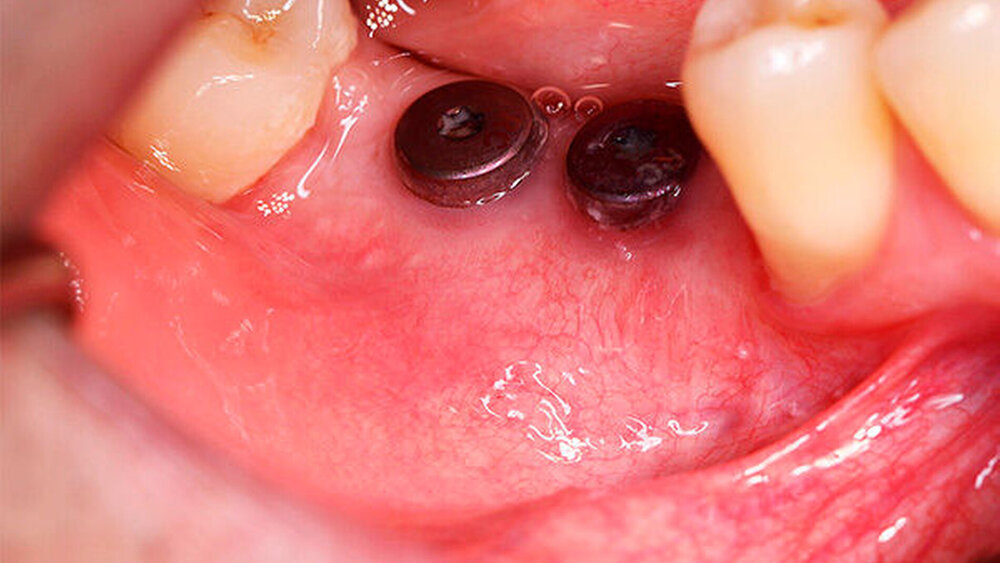

Nach missglückter Augmentation im rechten Oberkiefer stellte sich ein 42-jähriger Patient in unserer Praxis vor. Für die gewünschten Implantate im rechten Oberkiefer regio 16 und 17 war vertikal deutlich zu wenig Knochen vorhanden. Ein Sinuslift hätte zwar die Höhe des Knochens wieder hergestellt, die prothetische Position der Zahnkronen wäre aber somit in einer Infraokklusion zu liegen gekommen oder die Implanatkronen hätten völlig überdimensioniert werden müssen. Daher entschied sich der Patient für die Rekonstruktion mittels allogenen CAD/CAM-Knochenblocks. Das Prozedere gestaltete sich wie in Fallbeispiel 1. Auch die Einheilzeiten wurden entsprechend eingehalten.

Ein 29-jähriger Patient stellte sich mit einer massiven Alveolarkammatrophie im rechten Unterkiefer in unserer Praxis vor. Diese lag in langen Jahren der Zahnlosigkeit begründet. Eine Beckenkammaugmentation kam für den Patienten nicht in Betracht. Dennoch wünschte er die Versorgung mit festsitzendem Zahnersatz. Nach ausführlicher Beratung entschied sich auch dieser Patient für eine Augmentation mit einem patientenindividualisierten allogenen CAD/CAM-gefertigten Knochenblock. Die DICOM-Daten des Unterkiefer-DVTs wurde an die Firma Zimmer gesendet, und es erfolgten wie im oben beschriebenen Fall eine virtuelle Planung und das virtuelle Design des allogenen Knochenblocks anhand der geplanten Implantatpositionen. Nach der üblichen Kontrolle und Freigabe des Chirurgen erfolgte die eigentliche Fertigung und Übersendung des Knochenblocks in die Praxis. Die Augmentation erfolgte auch in diesem Fall in Vollnarkose unter antibiotischer Abschirmung perioperativ mit Ampicillin. Die Schnittführung im Unterkiefer unterscheidet sich von der Sockelschnittführung im Oberkiefer aufgrund der Anatomie (N. mentalis). Auch bei diesem Patienten wurde eine tief im Vestibulum liegende bogenförmige Inzi‧sion durchgeführt, jedoch ohne die vertikalen Entlastungen. Nach streng subperiostaler Präparation erfolgte die Darstellung des N. mentalis. Die Vorbereitung des Spenderbetts sowie die Wässerung, Einpassung und Befestigung des allogenen Knochenblocks gestalteten sich wie im Fallbeispiel 1. Die Heilzeit des Knochenblocks dauerte ebenfalls sechs Monate. Zwei Implantate (Straumann) wurden nach krestaler Schnittführung in Lokalanästhesie eingebracht und heilten subgingival binnen drei Monaten ein. Aufgrund des massiven Volumenzuwachses war auch ebenfalls eine Vestibulumplastik im Zuge der Implantatfreilegung notwendig. Das Prozedere verlief ebenfalls wie im Fallbeispiel 1. Das freiliegende Gewebe wurde mit einer Kollagenmatrix abgedeckt. Dadurch konnte die Breite der befestigten Gingiva deutlich verbreitert werden.